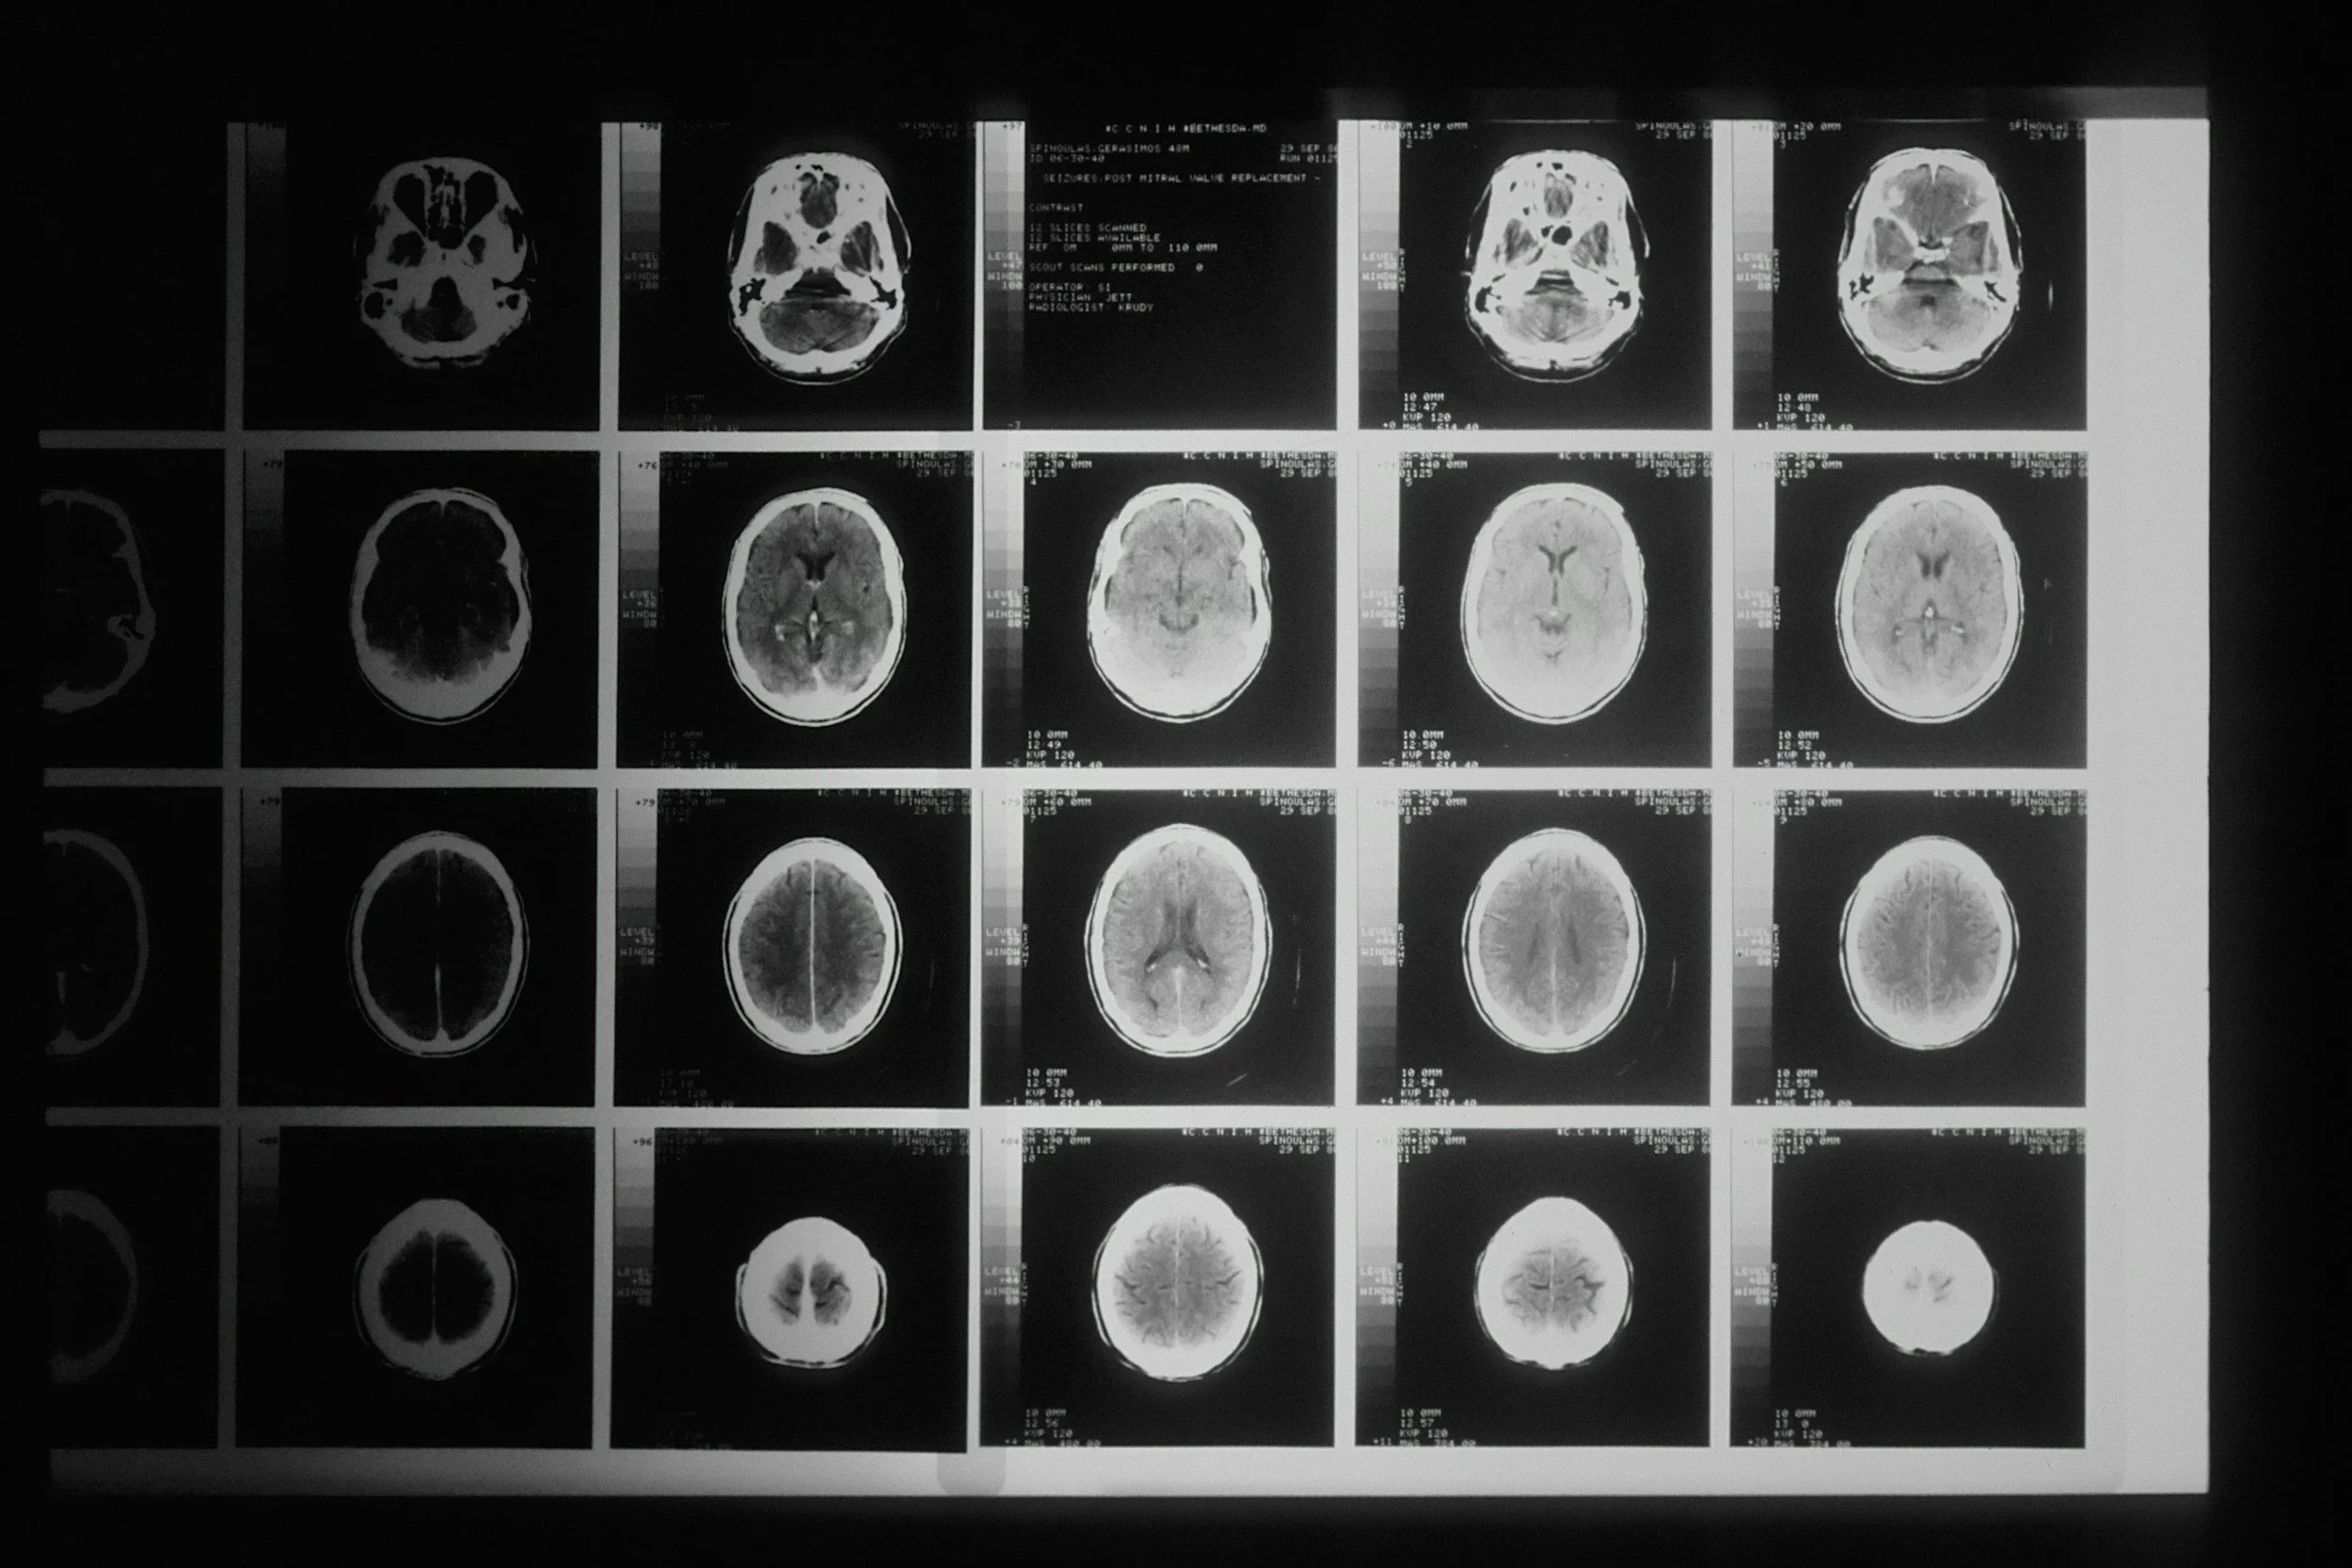

SUDEP most often occurs following a generalized tonic-clonic seizure, frequently during sleep. While research is ongoing, evidence suggests that respiratory suppression, cardiac arrhythmias, and post-seizure brain shutdown may contribute. Each year, more than 3,400 people in the United States die from SUDEP, making it the leading cause of epilepsy-related mortality and responsible for more deaths annually than fires or Sudden Infant Death Syndrome (SIDS).

Epilepsy is one of the most common neurological disorders in the United States and affects individuals across every age, background, and community.